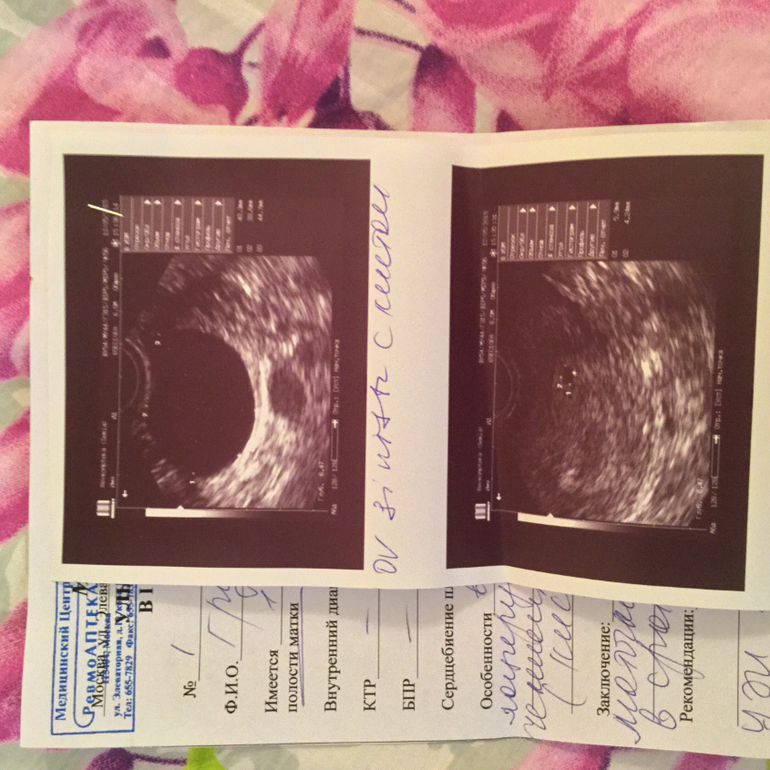

Беременность- 1 триместр ( только до 10 недель)Только что пришла с УЗИ, всё посмотрели, нашли кисту в левом Я. А ещё сказали, что низкое прикрепление...это опасно? Запретили ходить в фитнес

А еще недели через три сделайте еще раз УЗИ,т.к. здесь у Вас написано,что сердцебиение не определяется,но это потому что маленький срок.Просто чтобы удостовериться,что все ок с маськой ☺